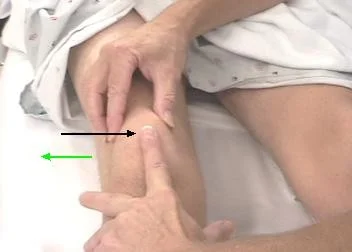

Collateral Ligament Testing

- Stress test with knee slightly flexed

- Alternative technique for collateral ligament testing